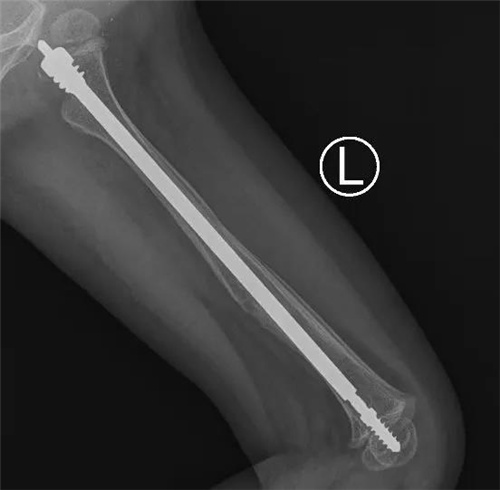

小儿骨科团队多次讨论后,决定采用一种专门针对成骨不全的全新手术方式:儿童可延长式髓内针内固定术。这种髓内针可以应用于大腿、小腿、上臂等长骨骨折。随着孩子的生长,可延长髓内针自动滑动延长,加强了患儿骨质的强度,减少再次骨折的几率。

在完善各项检查和准备后,小儿骨科团队在麻醉科、手术室的配合下为彤彤进行了微创手术。术中,主刀医生小儿骨科主任董震将直径为3.0mm的针芯和4.8mm的可延长弹性髓内钉系统,精准的置入股骨髓腔内完成复位和固定。手术耗时仅1.5个小时,骨折部位并无手术切口,仅在远离骨折的肢体近端有个微创手术切口,术中出血仅5ml。目前彤彤恢复良好,已经康复出院。